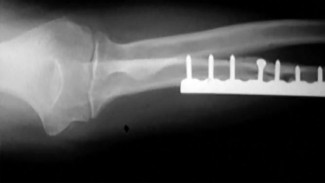

- الأشعة السينية (X-rays): هي الخطوة الأولى في تقييم الكسور، الخلوع، وتغيرات التهاب المفاصل. تساعد في تحديد مدى تدهور العظام والمسافات المفصلية. على سبيل المثال، تُظهر صور الأشعة السينية كسور السلاميات

أو كسور قاعدة العظم المشطي الخامس

، بالإضافة إلى علامات مثل "الدمعة الشعاعية" (Radiographic Teardrop) في الرسغ التي تمثل الزاوية الزندية الراحية الحرجة للكعبرة البعيدة

. - الأشعة المقطعية (CT Scan): توفر صوراً تفصيلية ثلاثية الأبعاد للعظام، وهي مفيدة جداً لتقييم الكسور المعقدة، مثل كسور العظم الخطافي (Hamate Hook Fracture) التي قد لا تظهر في الأشعة السينية العادية